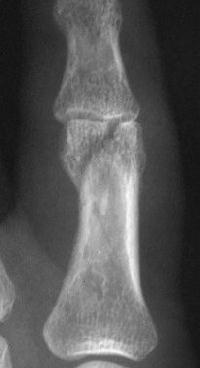

Unicondylar fractures of the phalangeal head are common, frequently unstable and unacceptably displaced. Although some may be treated successfully with percutaneous reduction and fixation, many require open reduction. In these cases, the screws were put right through the collateral ligament and sunk into the cortex. I think the simplest way to do this is to reduce and stabilize with two K wires, then remove the wires and replace with screws, one at a time, so reduction is maintained throughout. 1mm=39/1000" Kwire, so doing the math, here is how you choose the right sized Kwire to use as both drill and provisional fixation:

Case 2.